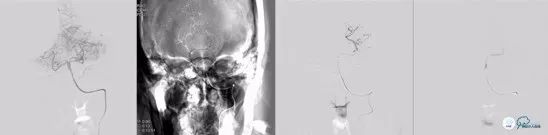

有股动脉穿刺置入6F 70cm血管长鞘至V2段,全身肝素化,置入5F 130cm NV导管至V4段,synchro导丝引导select plus 微导管通过血栓段至左侧大脑后动脉P2段,微导管造影确认真腔后,跨越闭塞段释放solitareAB 6-30取栓支架,等待5分钟,中间导管在支架锚定下引导至基底动脉尖端部,保持负压抽吸,先超选到左侧大脑后动脉P1段进行取栓。

图6

对左侧大脑后动脉取栓后后复查造影提示:左侧大脑后动脉恢复前向血流mTICI3级;右侧大脑后动脉P1远端未见显影。与左侧进行相同操作;synchro导丝引导select plus 微导管通过血栓段至右侧大脑后动脉P2段,微导管造影确认真腔后,跨越闭塞段释放solitareAB 6-30取栓支架,等待5分钟,中间导管在支架锚定下引导至基底动脉尖端部,保持负压抽吸,先超选到右侧大脑后动脉P1段进行取栓。

图7

取栓后复查造影提示:基底动脉级双侧大脑后动脉前向血流mTICI 3级,血管腔内未见血栓级狭窄影像,左侧椎动脉通道未见明显痉挛、夹层等影像。

图8